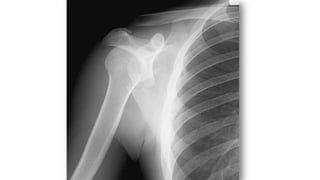

LUXACIÓN HOMBRO

• La articulación glenohumeral posee el mayor grado de movilidad del

aparato locomotor

• Mecanismo: abducción forzada acompañada de una rotación

externa del brazo

• En ancianos, suele estar acompañada por la avulsión del troquíter

• Es la articulación que se luxa con más frecuencia

• Tipos

– Luxación anterior: más frecuente. Dolor, impotencia funcional,

parestesias. “Hombro en charretera”. Se asocia a Fx troquíter

– Luxación posterior: más frecuente en ancianos. Muy dolorosa

– Luxación erecta/inferior: “saludo hitleriano”

– Luxación superior: muy rara. Requiere fractura asociada